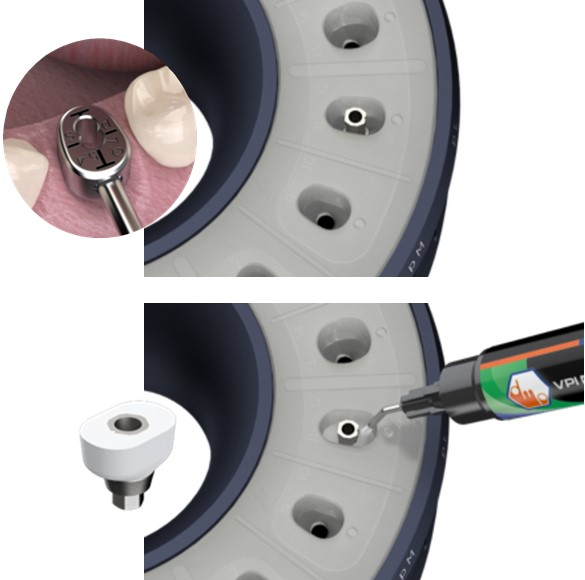

Pasul 3 – Procesul de fabricare a pilonului de vindecare personalizat

Rotește inelul superior al matriței până când forma/ dimensiunea dorită a puțului de silicon este aliniată la inserția protetică VPI dorită, prezentă în baza matriței.

Poziția fiecărei inserții de conexiune protetică VPI în interiorul bazei matriței ar trebui să fie disponibilă pe fișa informativă care însoțește kitul matriței. Acest lucru va facilita procesul de identificare a poziției inserțiilor de conectare de tip implant pentru asistent.

Pasul 4 – Procesul de fabricare a pilonului de vindecare personalizat

Asistentul instalează un bont temporar în puțul matriței cu codul corespunzător (E.g pS) la cel din fila de formă anatomică a ghidului (E.g pS).

El / Ea introduce apoi materialul compozit adecvat în spațiul deschis și vindecă ușor cu unul sau mai multe trepte.

Apoi dezinstalează bontul personalizat de vindecare creat și continuă cu lustruirea suprafeței compozite și dezinfectarea corespunzătoare.

Procesul de fabricare a bontului de vindecare personalizat se poate face după programarea consultației sau chiar la o intervenție chirurgicală, deoarece necesită doar aproximativ 4 minute pentru a fi finalizată.